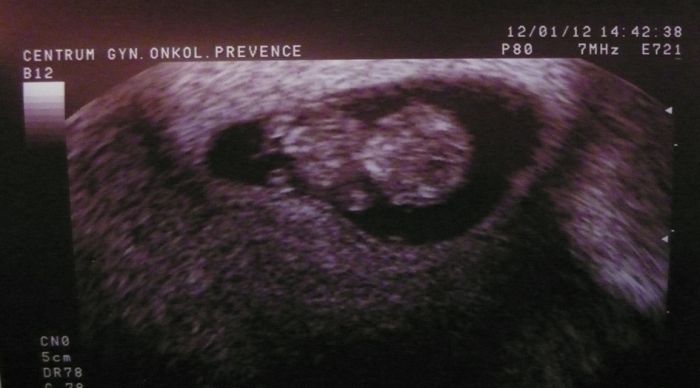

Ahoj holky...tak jsem byla dneska na tom vyšetření děložního čípku (kvůli dřívější konizaci) a poprosila jsem doktora, aby se podíval ma mimčo. Tak jsem viděla to mrskající se tělíčko, srdíčko bilo a odpovídá stáří podle početí ;-) Dneska jsem 9+4.

Hrozně se mi ulevilo a mám šílenou radost.

Gratuluji Blani

pekna fotecka ted uz to bude vsechno v poradku ...

[78442] jezkovy voci Blani, to je nadhernej obrazek!! Ja bych taky takovej chtela......ja mela zamlkle tehu prave v 9 tt, a nebylo videt vubec nic, ted vidim, co tam vlastne melo bejt a nebylo.......opravdu krasne. A mimco sebou fakt uz mrskalo???

[78448] Díky Lucinečko :-) ...já tomu taky věřím že teď už to bude oukej!! :-) Strašně se na to maličké těšíme. Už teď ho milujem z celého srdíčka!

[78450] Jo jo...viděla jsem, jak se hýbalo a jak tepalo srdíčko. Nádherný pocit!! Ono je to vlastně už 10. týden. Páč je to celých 9 týdnu + ty 4 dny.

Blani moc krásná fotečka .